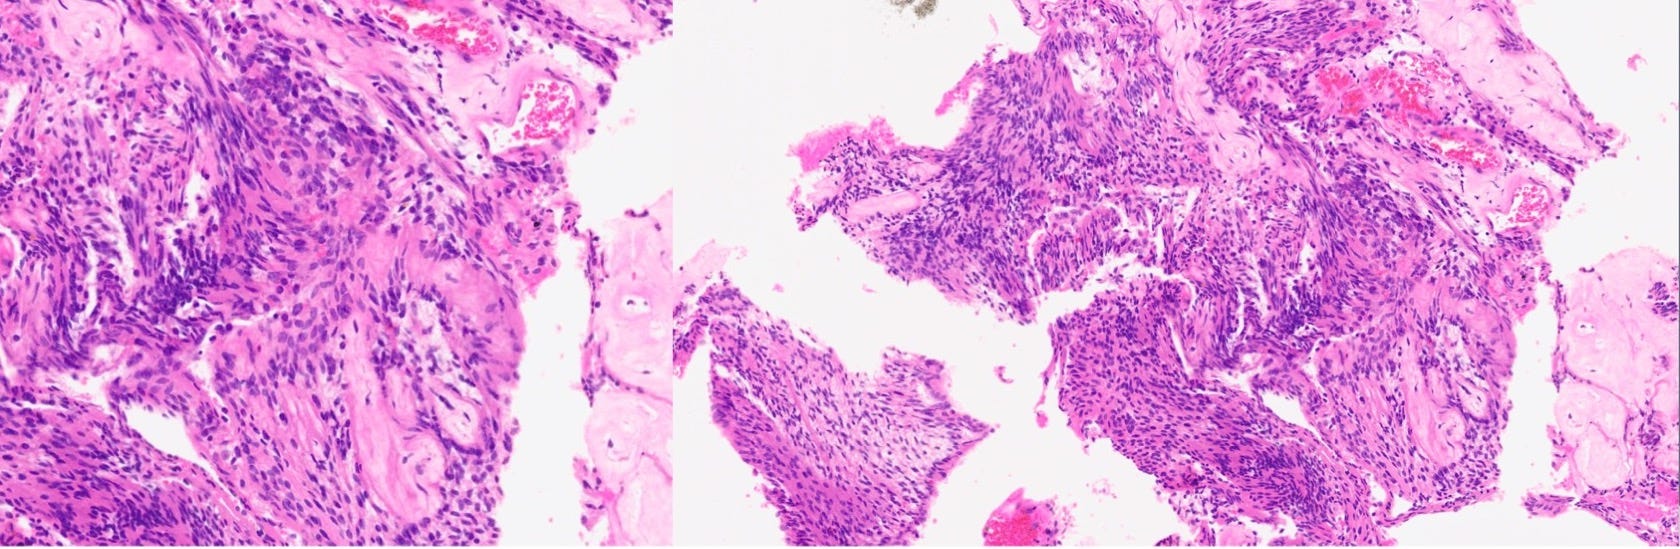

Case 23: An Incidental Posterior Mediastinal Mass

A 39-years old was found to have a mass in the chest on a CT chest done for COVID-19.

What is the likely diagnosis?